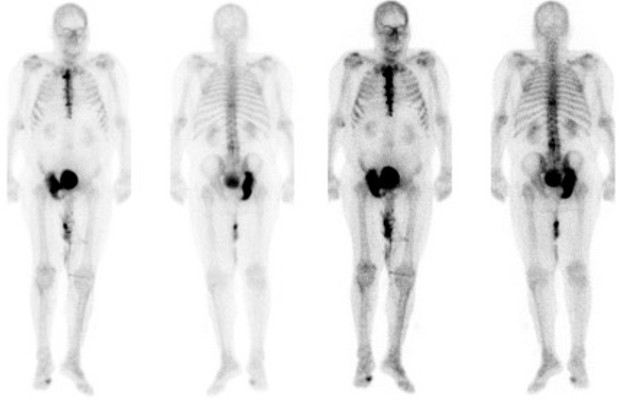

Die führende Ursache für den tumorassoziierten Tod ist die Metastasierung. Bis zu 70 % der fortgeschrittenen malignen Tumorentitäten bilden Knochenmetastasen. Ossäre Metastasen sind oft nicht heilbar, sind mit Frakturen, Behinderungen, Schmerzen, eingeschränkter Lebensqualität und einer schlechten Prognose assoziiert. Haben sich Metastasen gebildet, können die Betroffenen zumeist nur noch mittels palliativer Zystektomie bzw. palliativer Chemotherapie behandelt werden.

Der Knochen ist eine prämetastatische Nische (PMN), die die Ansiedlung, das Überleben und die Kolonisierung von metastasierenden Tumorzellen unterstützt. Darüber hinaus ist der Knochen ein homöostatisches Gewebe, dass ständigen Auf- und Abbauprozessen unterlegen ist. Auch im Rahmen dieser Umbauprozesse kommt es zu einer Freisetzung von Zytokinen und Wachstumsfaktoren wie z. B. RANK-L, IGFs, Kalzium und TGF-β. Diese Faktoren sind maßgeblich an der Proliferation, Migration und Metastasierung und an der malignen Wechselwirkung („Teufelskreis“) von Tumor- und Knochenzellen beteiligt.